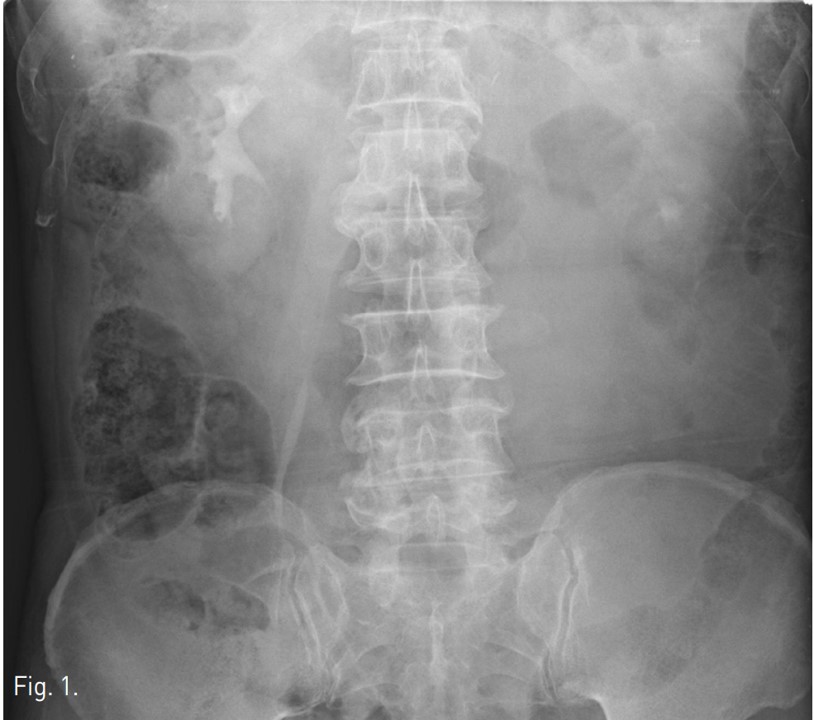

ESWL 시술 전 촬영한 KUB상 좌측 콩팥의 하극 부위의 콩팥돌로 보이는 고음영이 있음(Fig. 1). ESWL 시술 후에 발생한 통증으로 시행한 전산화단층촬영(CT)에서 좌측 콩팥주위 공간에 큰 혈종이 있으며 이로 인해 콩팥이 앞쪽으로 밀렸으며, 출혈로 보이는 조영제 누출이 있음(Fig. 2).

Fig. 2.

Fig. 2. Contrast enhanced CT shows contrast extravasation within large hematoma in left perirenal space.